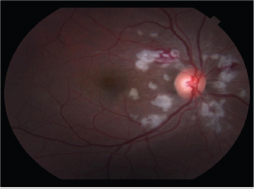

The patient followed up 3 days later complaining of para central scotoma and visual acuity of 20/30 in the right eye. At this time, the dilated exam revealed pronounced, peripapillary yellow-white patches consistent with Purtscher flecken and cotton wool spots in the right eye only. There was also an intraretinal hemorrhage along the superior arcade and an abnormal foveal reflex in the affected eye. With this constellation of findings, Purtscher’s retinopathy was diagnosed and the decision was made to observe for clinical improvement. Given the clinical diagnosis, fluorescein angiography was deferred.

Figure 1A: Fundus photo right eye 3 days after the accident showing polygonal white lesions in a peripapillary distribution, and area of intraretinal hemorrhage along the superior arcade.

Figure 1B: Fundus photo of the right eye 10 days after the accident showing similar, more defined white lesions.